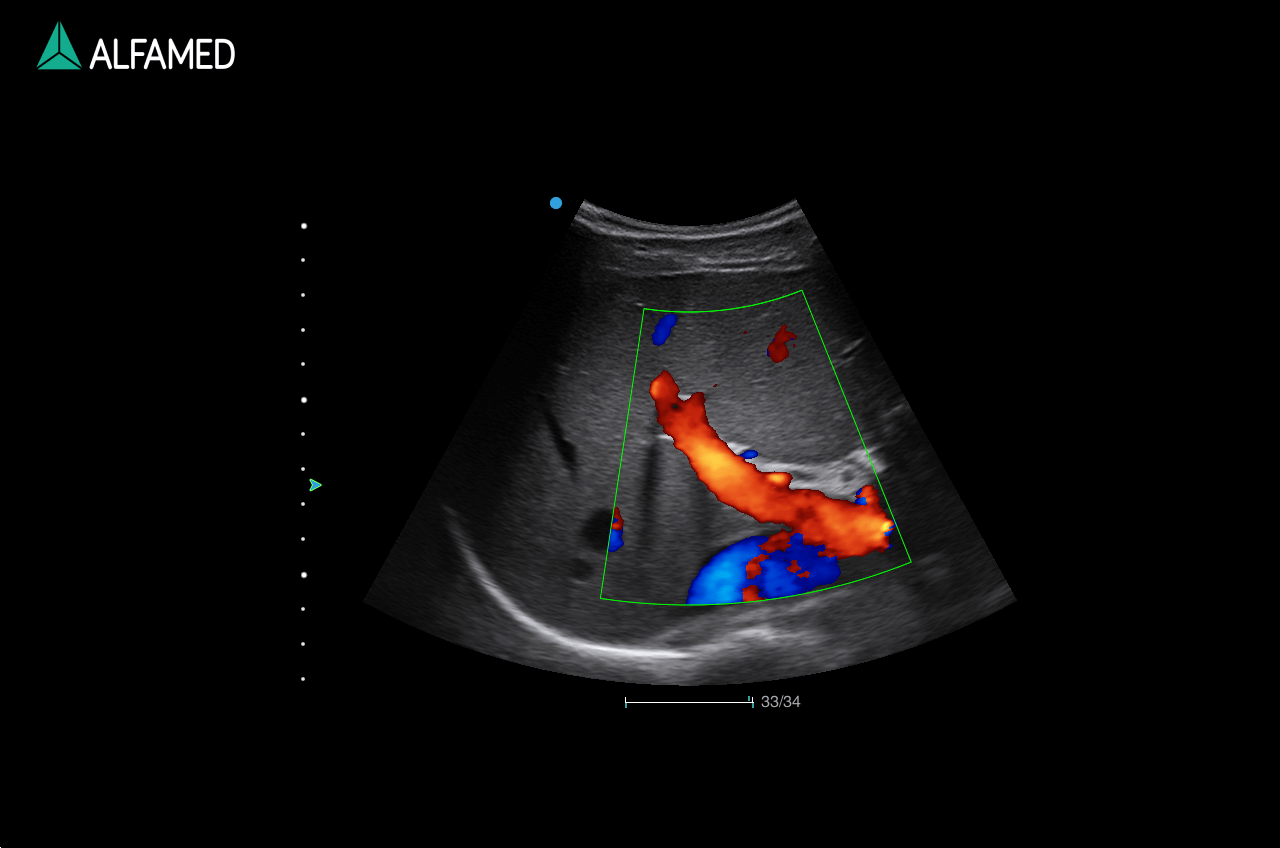

Dotado de softwares avançados e transdutores específicos, o Magnus X5 apresenta alta versatilidade para imagem geral e excelente performance, principalmente, nos exames de cardiologia avançada e obstetrícia.

- Panoscope com Color

- VS Flow